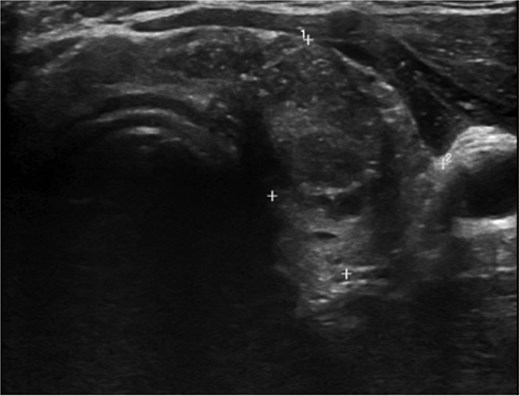

A 36-year-old gentleman presented to our clinic with a 1-month history of neck swelling, without any other complaints. The patient was medically and surgically free, had no family history or risk factors for thyroid cancer. Thyroid function tests revealed a normal thyroid-stimulating hormone (TSH) of 2.05 μIU/mL, which was within the normal range. The patient’s remaining laboratory results showed an elevated free thyroxine (T4) level of 26.7 pmol/L (reference range: 10.3–24.5 pmol/L). Corrected calcium was low at 2.03 mmol/L (reference range: 2.10–2.55 mmol/L), while magnesium, vitamin D, and albumin levels were within the normal range. Ultrasound of the neck, revealed a right lobe hypoechoic nodule 0.5 × 0.4 cm classified as TI-RADS 4. As well as a left lobe lesion measuring 2.3 × 1.7 cm, classified as TI-RADS 5 (Figs 1 and 2). Fine needle aspiration of the left lobe nodule confirmed the diagnosis of papillary thyroid carcinoma.